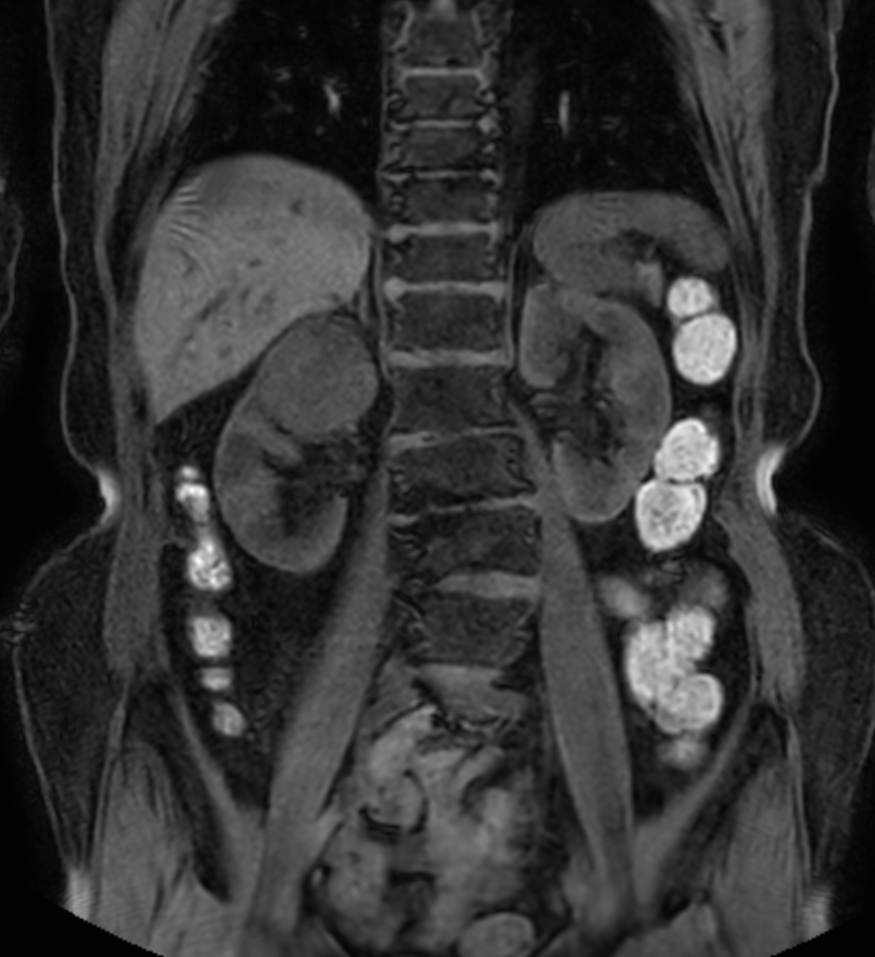

Patient with a kidney lesion. The ExamCard includes techniques for 3D imaging (PelvisVIEW, eTHRIVE) allowing for multiple image directions in one single scan, efficient fat-free imaging over large field-of-views (mDIXON XD), a multi-phase contrast-enhanced sequence (4D FreeBreathing) to improve imaging confidence and Compressed SENSE to accelerate the entire exam.

T2w TSE

DWI b800

DWI b800 (ADC)